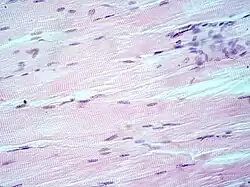

H&E is the combination of two histological stains: hematoxylin and eosin. The hematoxylin stains cell nuclei a purplish blue, and eosin stains the extracellular matrix and cytoplasm pink, with other structures taking on different shades, hues, and combinations of these colors.[5][6] Hence a pathologist can easily differentiate between the nuclear and cytoplasmic parts of a cell, and additionally, the overall patterns of coloration from the stain show the general layout and distribution of cells and provides a general overview of a tissue sample's structure.[7] Thus, pattern recognition, both by expert humans themselves and by software that aids those experts (in digital pathology), provides histologic information.

Hematoxylin principally colors the nuclei of cells blue or dark-purple,[6][15][14] along with a few other tissues, such as keratohyalin granules and calcified material. Eosin stains the cytoplasm and some other structures including extracellular matrix such as collagen[5][7][14] in up to five shades of pink.[8] The eosinophilic (substances that are stained by eosin)[5] structures are generally composed of intracellular or extracellular proteins. The Lewy bodies and Mallory bodies are examples of eosinophilic structures. Most of the cytoplasm is eosinophilic and is rendered pink.[10][15] Red blood cells are stained intensely red.

The structures do not have to be acidic or basic to be called basophilic and eosinophilic; the terminology is based on the affinity of cellular components for the dyes. Other colors, e.g. yellow and brown, can be present in the sample; they are caused by intrinsic pigments such as melanin. Basal laminae need to be stained by PAS stain or some silver stains, if they have to be well visible. Reticular fibers also require silver stain. Hydrophobic structures also tend to remain clear; these are usually rich in fats, e.g. adipocytes, myelin around neuron axons, and Golgi apparatus membranes.